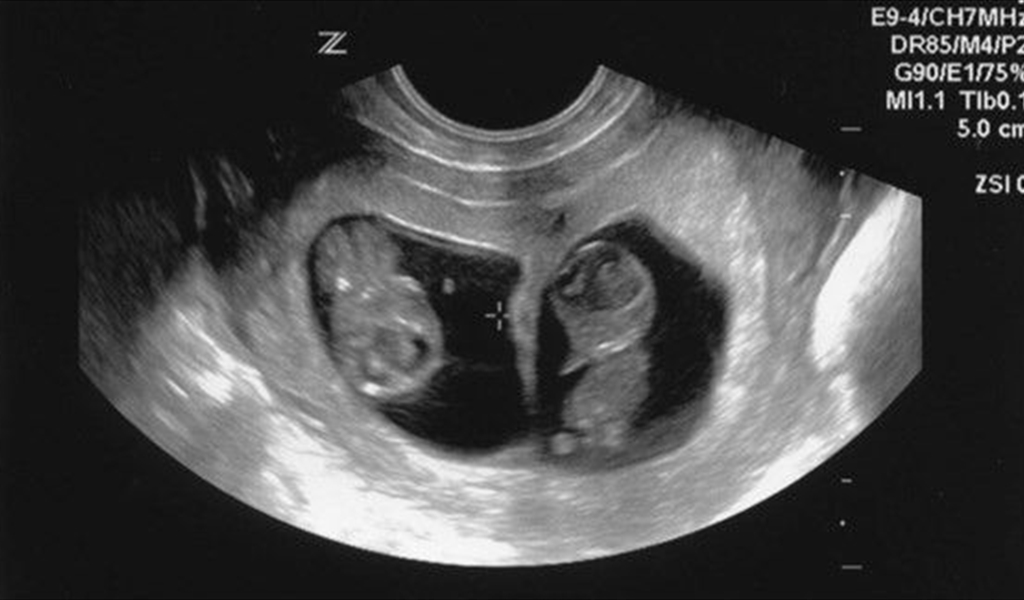

الجريبات: أول علامات الحمل التي يمكن رؤيتها عن طريق الفحوصات هي جريبات الحمل (كيس الحمل)، والتي تبدو بيضاوية الشكل في تصوير الألتراساوند. بعد مرور 4 أسابيع من الحمل يمكن رؤية جريبين (كيسين) إذا كان الحمل بتوأم غير متطابقين. أما التوأم المتطابق فينمو في جريب واحد، ولا يمكن رصدهما قبل الأسبوع الـ5 عن طريق الألتراساوند.